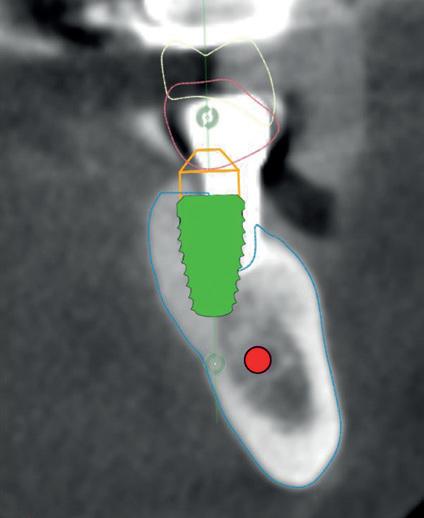

RECONFIGURAREA suportului osos implantar. În cazul prezentat, după ani de terapie ortodontică incorect executată, dezvoltarea dentară a pacientului a complicat obținerea unui zâmbet estetic. S-a reanalizat și s-a optat pentru abordare interdisciplinară care cuprinde chirurgia parodontală, un al doilea tratament

ortodontic și protetica pentru a oferi îngrijirea comprehensivă.

RECUPERAREA planului implantar original. Dacă unul sau mai multe implanturi planificate eșuează, perspectiva reimplantării în locația compromisă poate fi simplificată prin transformarea ghidului chirurgical la nivel osos într-un ghid chirurgical suportat de implanturi în momentul intervenției chirurgicale primare.